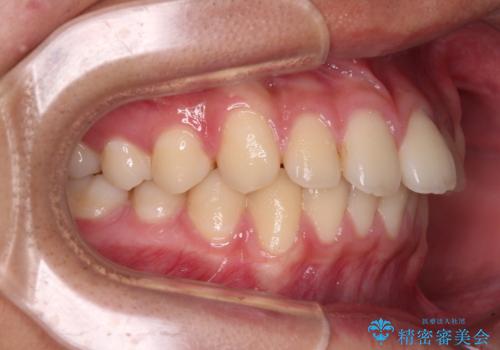

下顎前歯が上顎前歯を突き上げるような咬み合わせとなっており、その影響で上顎正中に隙間ができている状態でした。

突き上げによる隙間を予防する為に、深い咬み合わせを改善するような治療計画としました。咬み合わせを改善させることはできましたが、隙間は後戻りしやすいので、通常の下顎前歯のみではなく、上顎前歯2本もワイヤーで保定を行いました。